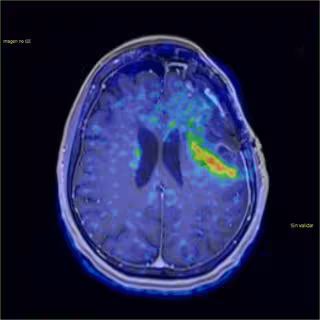

Imagen tumor cerebral

GOBIERNO DE ASTURIAS - Archivo